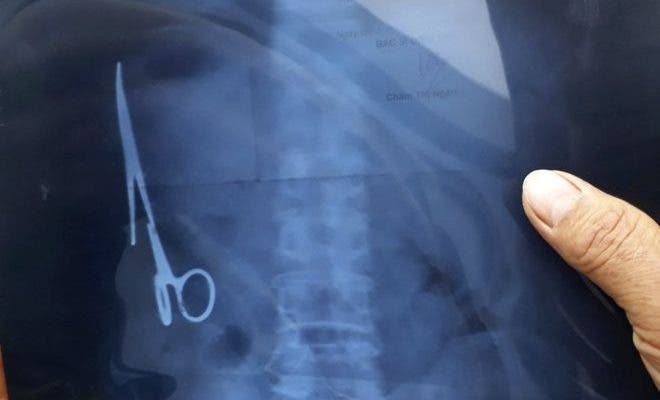

Retiran tijeras del estómago de un hombre después de 18 años

Un hombre de 54 años, acudió al médico tras un dolor abdominal que no respondía a los analgésicos. Cuando los médicos realizaron los debidos estudios, encontraron unas tijeras de 15 centímetros dentro de su estómago.

En 1998, el hombre había sido sometido a una operación tras un accidente de coche, donde posiblemente se olvidaron las tijeras que se extrajeron el mes pasado, en el hospital Gang Thep de Thai Nguyen, en el norte de Vietnam.

Casi 18 años después, el instrumento quirúrgico se fue oxidando y se alojó cerca de su colon, sin embargo el hombre continuó con una vida normal.